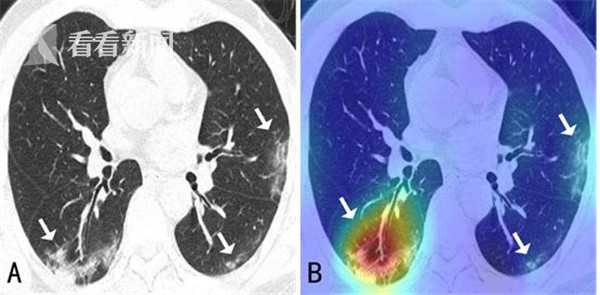

新型冠状病毒引起的肺炎,与其他病毒性肺炎、细菌性肺炎在CT影像呈现上有诸多相似之处。三种肺炎都存在视觉相似的病灶(如磨玻璃影),目前临床发现可适当利用病灶在肺部空间的分布等更多差异信息进行区分。

“现阶段医生需要在大量的影像数据中快速诊断出新冠肺炎的病例,此外还需要诊断出病灶分布的位置、大小等来评估严重程度。”薛向阳介绍,针对临床的现实需求,团队将设计目标定位于“肺炎分类鉴别”和“关键病灶检测”两大功能,前者是为区别健康状态、新冠肺炎、其他病毒性肺炎、细菌性肺炎,后者则为找到并分隔出磨玻璃影等病灶区域。

而由于CT影像切片中的病灶区域有大有小,且往往大中小病灶区域面积悬殊,如何使算法能同时检测大、中、小各个目标是另一大难题。团队利用神经网络的层次性特点与病灶区域的大小进行对应,“网络的底层关注细节,即小病灶区域,而网络中层到高层所关注的病灶区域则越来越大,因此模型通过不同层次的加权和融合,最终便能达到同时检测大小病灶区域的目标。”薛向阳解释道。